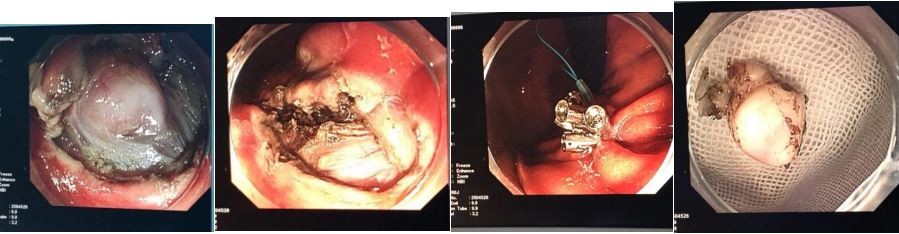

3.内镜下消化道黏膜切除术(EMR)黏膜剥离术(ESD)、黏膜下肿物挖除术(ESE)

胃肠道早期肿瘤的诊疗是我科近年重要发展方向,并取得较好的成绩。首先,我科开展了血清胃功能检查及胃肠镜精细检查进行食管、胃及大肠早癌筛查。其次,采用EMR及ESD技术对内镜下消化扁平状息肉、较大息肉及消化道癌前病变、早期癌等进行内镜下微创治疗。对于黏膜下的肿物则采用黏膜下挖除术(ESE)。

内镜下早癌的发现及内镜下黏膜剥离术(ESD)

内镜下黏膜下肿物挖除术(ESE)、荷包缝合技术